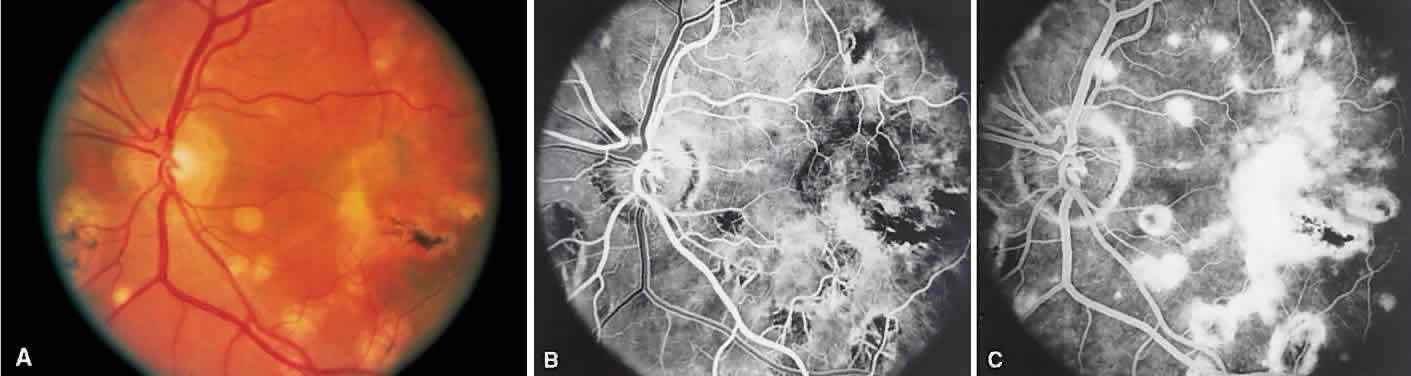

BIRDSHOT RETINOCHOROIDOPATHY

Birdshot retinochoroidopathy (also known as vitiliginous chorioretinitis) presents bilaterally, generally in middle-aged women, causing floaters and decreased vision, night blindness, and color blindness. Clinically, there are patches of postequatorial choroidal and retinal pigment epithelial depigmentation (Fig. 10A), vitreous cells, macular and disc edema, and venous sheathing. SRNV frequently is a late sequela. Often central vision may be preserved in at least one eye.

Fig. 10. Birdshot retinochoroidopathy. A. Multiple cream-color deep choroidal lesions. B. Fluorescein angiogram shows leakage of the optic disc and the retinal vasculature. C. Indocyanine green angiography showing areas of hypofluorescence that exceed those observed on fluorescein angiography.

On fluorescein angiography, retinal vessel staining, disc leakage, and cystoid macular edema are found (see Fig. 10B). There often is generalized hypofluorescence of the retinal vessels and increased circulation time.35,36 Surprisingly, the patches of depigmentation may appear normal on angiography, although there can be mild late hyperfluorescence.35,36 Posterior pole choroidal hyperfluorescent lesions that correspond to the areas of depigmentation and SRNV also can be seen.37

On ICG angiography (see Fig. 10C), early and late hypofluorescent patches, exceeding the clinically detectable lesions, with a choroidal vasotropic distribution and relative sparing of the peripapillary area and the central macula, are noted. These findings differentiate this condition from AMPPPE, multifocal choroiditis, and other granulomatous conditions such as sarcoidosis and sympathetic ophthalmia. Rarely, hyperfluorescent spots are noted in the late phases of the angiogram, which correspond ophthalmoscopically to retinal inflammation or obstructive changes.38